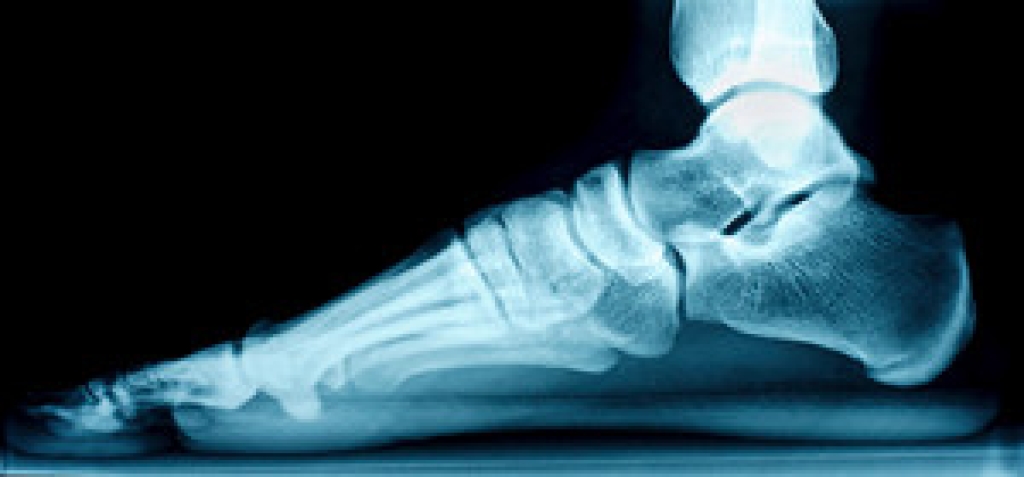

The Achilles tendon is a tendon that connects the lower leg muscles and calf to the heel of the foot. It is the strongest tendon in the human body and is essential for making movement possible. Because this tendon is such an integral part of the body, any injuries to it can create immense difficulties and should immediately be presented to a doctor.

Achilles tendon injuries are diagnosed by a thorough physical evaluation, which can include an MRI. Treatment involves rest, physical therapy, and in some cases, surgery. However, various preventative measures can be taken to avoid these injuries, such as: